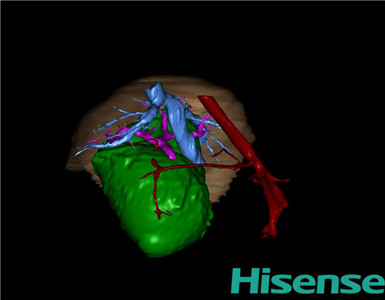

CT结果输入海信CAS系统后行3D重建及手术规划后,于2015-11-19全麻下行“胆总管囊肿切除+胆囊切除+胆总管-空肠吻合术”手术治疗:

将0.625mm双源薄层CT资料的静脉期和动脉期Dicom格式文件导入海信CAS系统。

通过调节窗宽窗位调整CT序号,对肝实质,胆囊,胆总管,下腔静脉,肝动脉、门静脉及肝静脉等进行三维重建;系统自动计算肝脏体积。

术前手术方案的规划。

术前三维重建:

重建图片